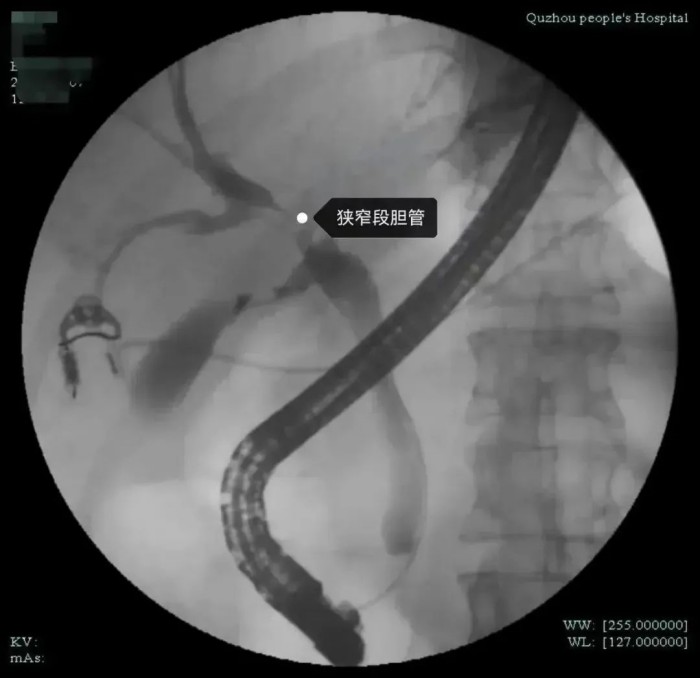

市人民醫(yī)院腫瘤放療科姜忠于主任醫(yī)師認(rèn)為目前不能排除腫瘤可能,需要做進(jìn)一步檢查,以明確診斷。同時(shí)肝膽外科袁磊博士和沈紅波主任醫(yī)師進(jìn)行會(huì)診。經(jīng)全面評(píng)估分析,醫(yī)生發(fā)現(xiàn)患者肝門(mén)部膽管狹窄,腫瘤標(biāo)記物不高,肝功能目前正常,狹窄局部無(wú)明顯腫塊,但仍不能排除膽道內(nèi)病變可能,決定對(duì)張女士行ERCP(內(nèi)鏡下逆行膽胰管造影術(shù))檢查,同時(shí)在ERCP下行經(jīng)口膽道鏡檢查。

經(jīng)過(guò)與張女士及其家屬詳細(xì)溝通后,在麻醉科、內(nèi)鏡中心的全力配合下,沈紅波為張女士實(shí)施了無(wú)痛經(jīng)口電子膽道鏡檢查。術(shù)中,沈紅波發(fā)現(xiàn)膽管狹窄處蒼白僵硬,黏膜表面雖然無(wú)明顯新生物,但仍不能排除膽管內(nèi)腫瘤的可能性。因此,他在膽道鏡探查的同時(shí)也取活檢和細(xì)胞刷檢,來(lái)鑒別是否是腫瘤。很快,術(shù)后活檢結(jié)果出來(lái)了,病理切片提示為惡性腫瘤。

經(jīng)口膽道鏡到底是一種什么樣的內(nèi)鏡呢?據(jù)介紹,經(jīng)口電子膽道鏡技術(shù)俗稱子母鏡,就是將一個(gè)更小、更精細(xì)的子鏡,經(jīng)過(guò)十二指腸鏡(母鏡)的孔道深入到膽管、胰管內(nèi),直視觀察膽管、胰管內(nèi)病變,為膽胰管疾病診療提供直視化、高清化、精確化的解決方案。

沈紅波介紹,我院率先在衢州地區(qū)引進(jìn)了經(jīng)口電子膽道鏡系統(tǒng),該設(shè)備可以進(jìn)入膽胰管內(nèi)進(jìn)行直視下的檢查,有利于早期發(fā)現(xiàn)病灶,精準(zhǔn)取活檢。直視電子膽道鏡的內(nèi)鏡直徑為9Fr(3毫米),可以進(jìn)入肝內(nèi)的3-4級(jí)膽管及胰管內(nèi)。既往傳統(tǒng)的十二指腸鏡無(wú)法進(jìn)入膽管內(nèi)進(jìn)行直視檢查治療,膽管內(nèi)結(jié)石等病變只能通過(guò)透視下的模糊影像辨認(rèn)。以前要想進(jìn)行膽道內(nèi)直視檢查,需借助腹腔鏡或經(jīng)皮經(jīng)肝膽道穿刺建立通道后才能將膽道鏡送入膽管,創(chuàng)傷大。但直視的電子膽道鏡可以通過(guò)十二指腸鏡鉗道內(nèi)進(jìn)入到膽管、胰管內(nèi)進(jìn)行直視下觀察病變、取活檢、碎石等治療,能夠早期發(fā)現(xiàn)微小病變,特別是對(duì)于膽胰腫瘤的早發(fā)現(xiàn)、早治療具有很高的臨床價(jià)值。